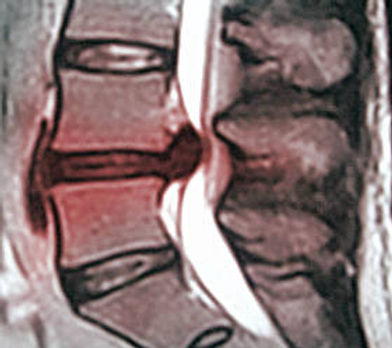

Large herniations are usually extrusions or sequestrations, where disc material has broken through the outer wall.

These look dramatic on MRI.

However, appearance does not automatically determine outcome.

Interestingly, larger extrusions often shrink more because more disc material is exposed to the immune system.